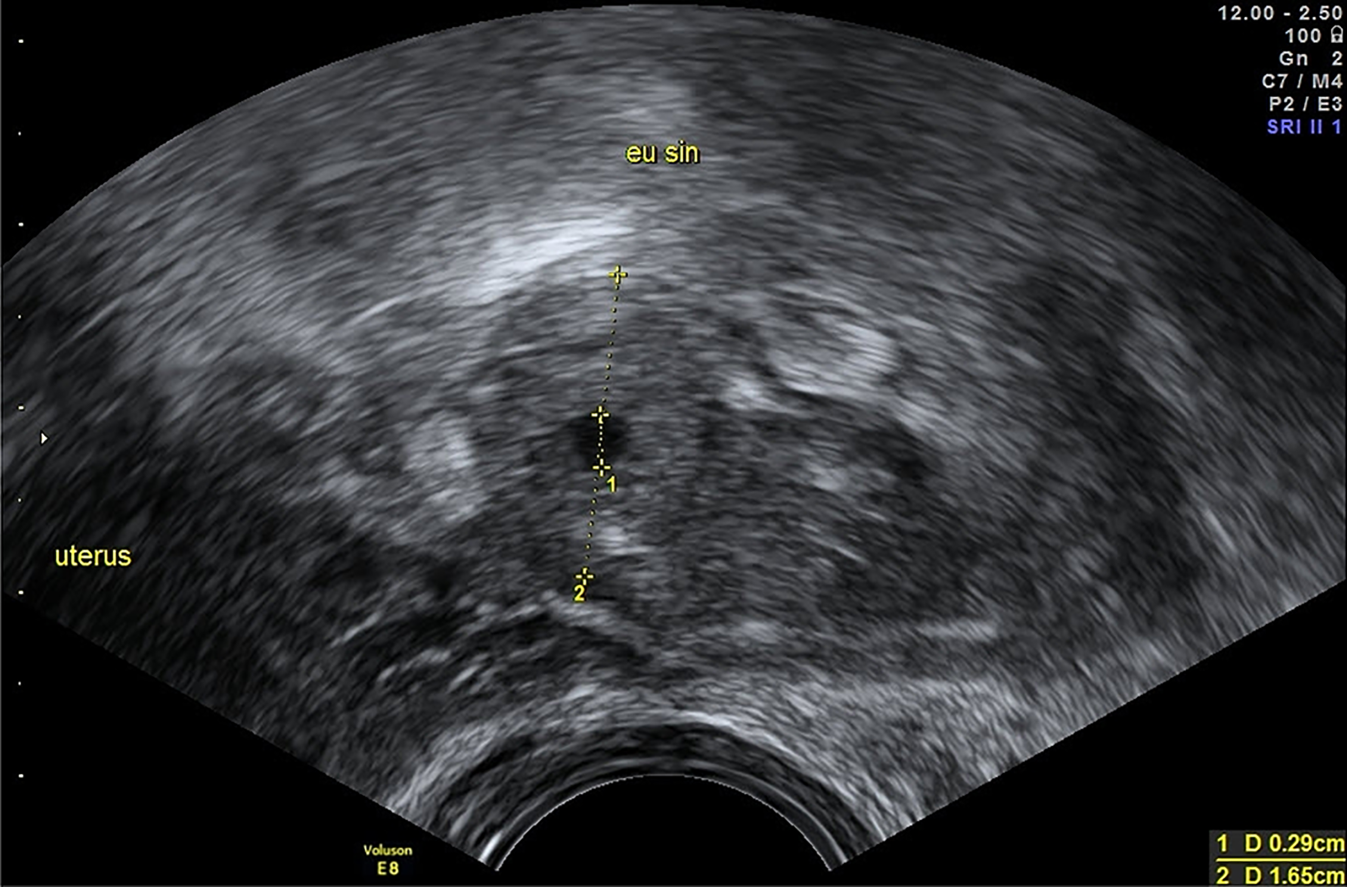

In den Anfangsjahren des Ultraschalls, als der Vaginalschall noch wenig verbreitet war, waren der Pseudofruchtsack und die freie Flüssigkeit im Douglas-Raum noch wichtige Erkennungsmerkmale, die den Verdacht auf eine EUG lenkten (Abb. 4). Der Pseudofruchtsack weist auf eine sekretorische Umwandlungsreaktion des Endometriums in Dezidua hin. Wenn er sich zeigt, dann als zentrale, unscharf begrenzte Flüssigkeitsansammlung entsprechend einer Serometra. Mit einem Fruchtsack sollte sie nicht verwechselt werden, da ein intakter früher Fruchtsack meist leicht exzentrisch im Cavum uteri liegt und am Rand eine markante, echodense deziduale Reaktion aufweist. Allerdings kann ein früher Spontanabort ein ähnliches sonographisches Bild aufweisen wie der Pseudofruchtsack.

Abb. 4

Zwei unsichere Marker für EUG: freie Flüssigkeit im Douglas (links im Bild) und ein „Pseudofruchtsack“ mit einer zentralen Flüssigkeitsansammlung im Cavum uteri (rechts im Bild). Beide treten nur bei zeitlich fortgeschritteneren EUG auf, wie im Fall von Abb. 1